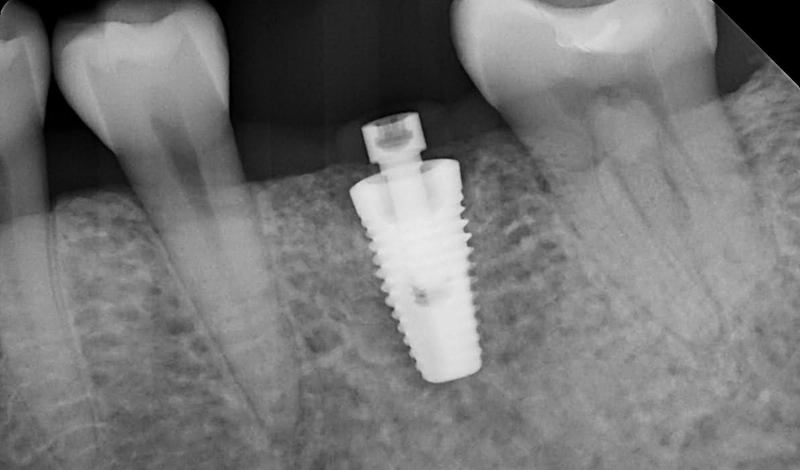

- Radiographs confirm that both implants (upper premolar and previously restored lower molar) are stable and well-integrated.

X-ray scans showing both implants placed in the upper premolar and lower molar positions